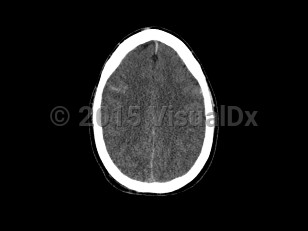

Cerebral edema

Cerebral edema is characterized by blurred vision, intracranial hypertension, headache, and loss of consciousness. Other common signs and symptoms are nausea, vomiting, sudden elevated blood pressure, mental status alteration, and decreased heart rate. It presents a life-threatening medical emergency leading to herniation, coma, and brain death.

Causes include severe brain trauma, ischemic stroke, meningitis, encephalitis, hepatic encephalopathy, brain cancer, diabetic ketoacidosis, eclampsia, or cerebral infarction. It also occurs as a form of high-altitude edema. Cerebral edema may occur in infants and adults.